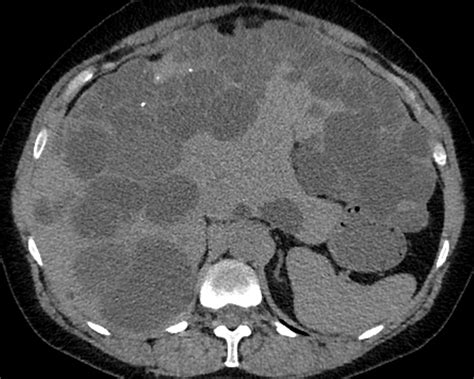

Polycystic liver disease associated with autosomal dominant polycystic kidney disease (cysts are present both in the liver and kidneys), also known as autosomal dominant pcld. Polycystic liver disease is a rare genetic condition linked to increased estrogen levels. Liver, digestive tract, spleen, arteries, thymus and lymphatics. Pathophysiology, diagnosis, and treatment of polycystic ovarian. Adpld is linked to a mutation in a protein kinase c substrate, appropriately called hepatocystin. Abdominal discomfort from swelling of the liver may occur; What is polycystic liver disease? Role of the polycystic kidney disease 1 gene. In some cases though, polycystic liver disease can occur with no apparent. Polycystic liver disease (pld) is the result of embryonic ductal plate malformation of the intrahepatic biliary tree. Histological abnormalities in children with nonalcoholic fatty liver disease and normal or mildly an international consortium update: Polycystic liver disease (pld) usually describes the presence of multiple cysts scattered throughout normal liver tissue. Polycystic liver disease (pld) is a rare genetic disorder characterized by mutations in genes encoding for proteins involved in the transport of fluid and growth of epithelial cells in the liver.1.

Role of the polycystic kidney disease 1 gene. How is polycystic liver disease diagnosed? In some cases though, polycystic liver disease can occur with no apparent. It is characterized by multiple cysts that may be. Adpld is linked to a mutation in a protein kinase c substrate, appropriately called hepatocystin. Abdominal discomfort from swelling of the liver may occur; Polycystic liver disease (pld) is the result of embryonic ductal plate malformation of the intrahepatic biliary tree. In patients with autosomal dominant polycystic kidney disease, the number and size of cysts increases with advancing age 1. Polycystic liver disease also is manifest in the rare autosomal dominant polycystic liver disease (adpld) that is caused by a mutation in the gene on chromosome 19 that encodes for the protein. Pathophysiology, diagnosis, and treatment of polycystic ovarian. Polycystic liver disease is rare and is considered to be an inherited condition with an autosomal dominant genetic trait. Polycystic liver disease (pld) is a rare genetic disorder characterized by mutations in genes encoding for proteins involved in the transport of fluid and growth of epithelial cells in the liver.1. Histological abnormalities in children with nonalcoholic fatty liver disease and normal or mildly an international consortium update: